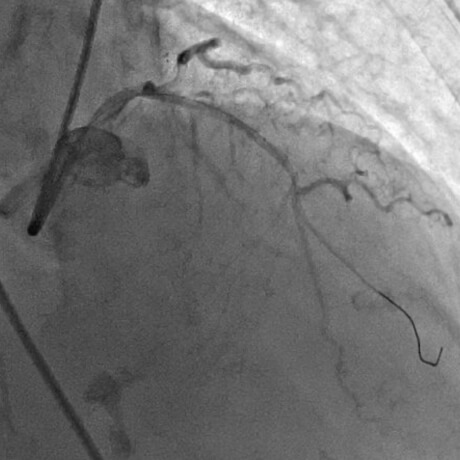

急性心筋梗塞症例へのPCI施行時の冠動脈造影画像

冠動脈が完全閉塞した急性心筋梗塞

ワイヤーの通過でわずかに血流改善